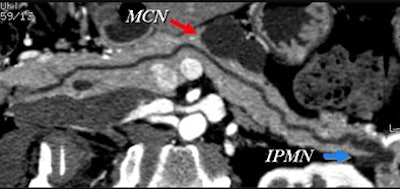

Certainly imaging-based diagnosis of the cysts has its limitations. For one thing, MDCT can diagnose six different pancreatic lesion types, including side branch intraductal papillary mucinous neoplasms (IPMNs), serous microcystic adenomas, epithelial cysts, mucinous cystic neoplasms, lymphatic cysts, and cystic islet cell tumors. But it can't always tell them apart.

Some lesion types look the same at CT, with overlapping appearance occurring, for example, between a mucinous cystic neoplasm and a thin-walled simple cyst that has no risk of malignancy. And mucinous cystic neoplasms are indistinguishable from benign epithelial cysts.

Small cystic lesions not worrisome for malignancy under 3 cm include side branch IPMNs, and serous microcystic adenomas, which are easily characterized by their honeycomb matrix that is also easily seen on ultrasound, Jeffrey said.